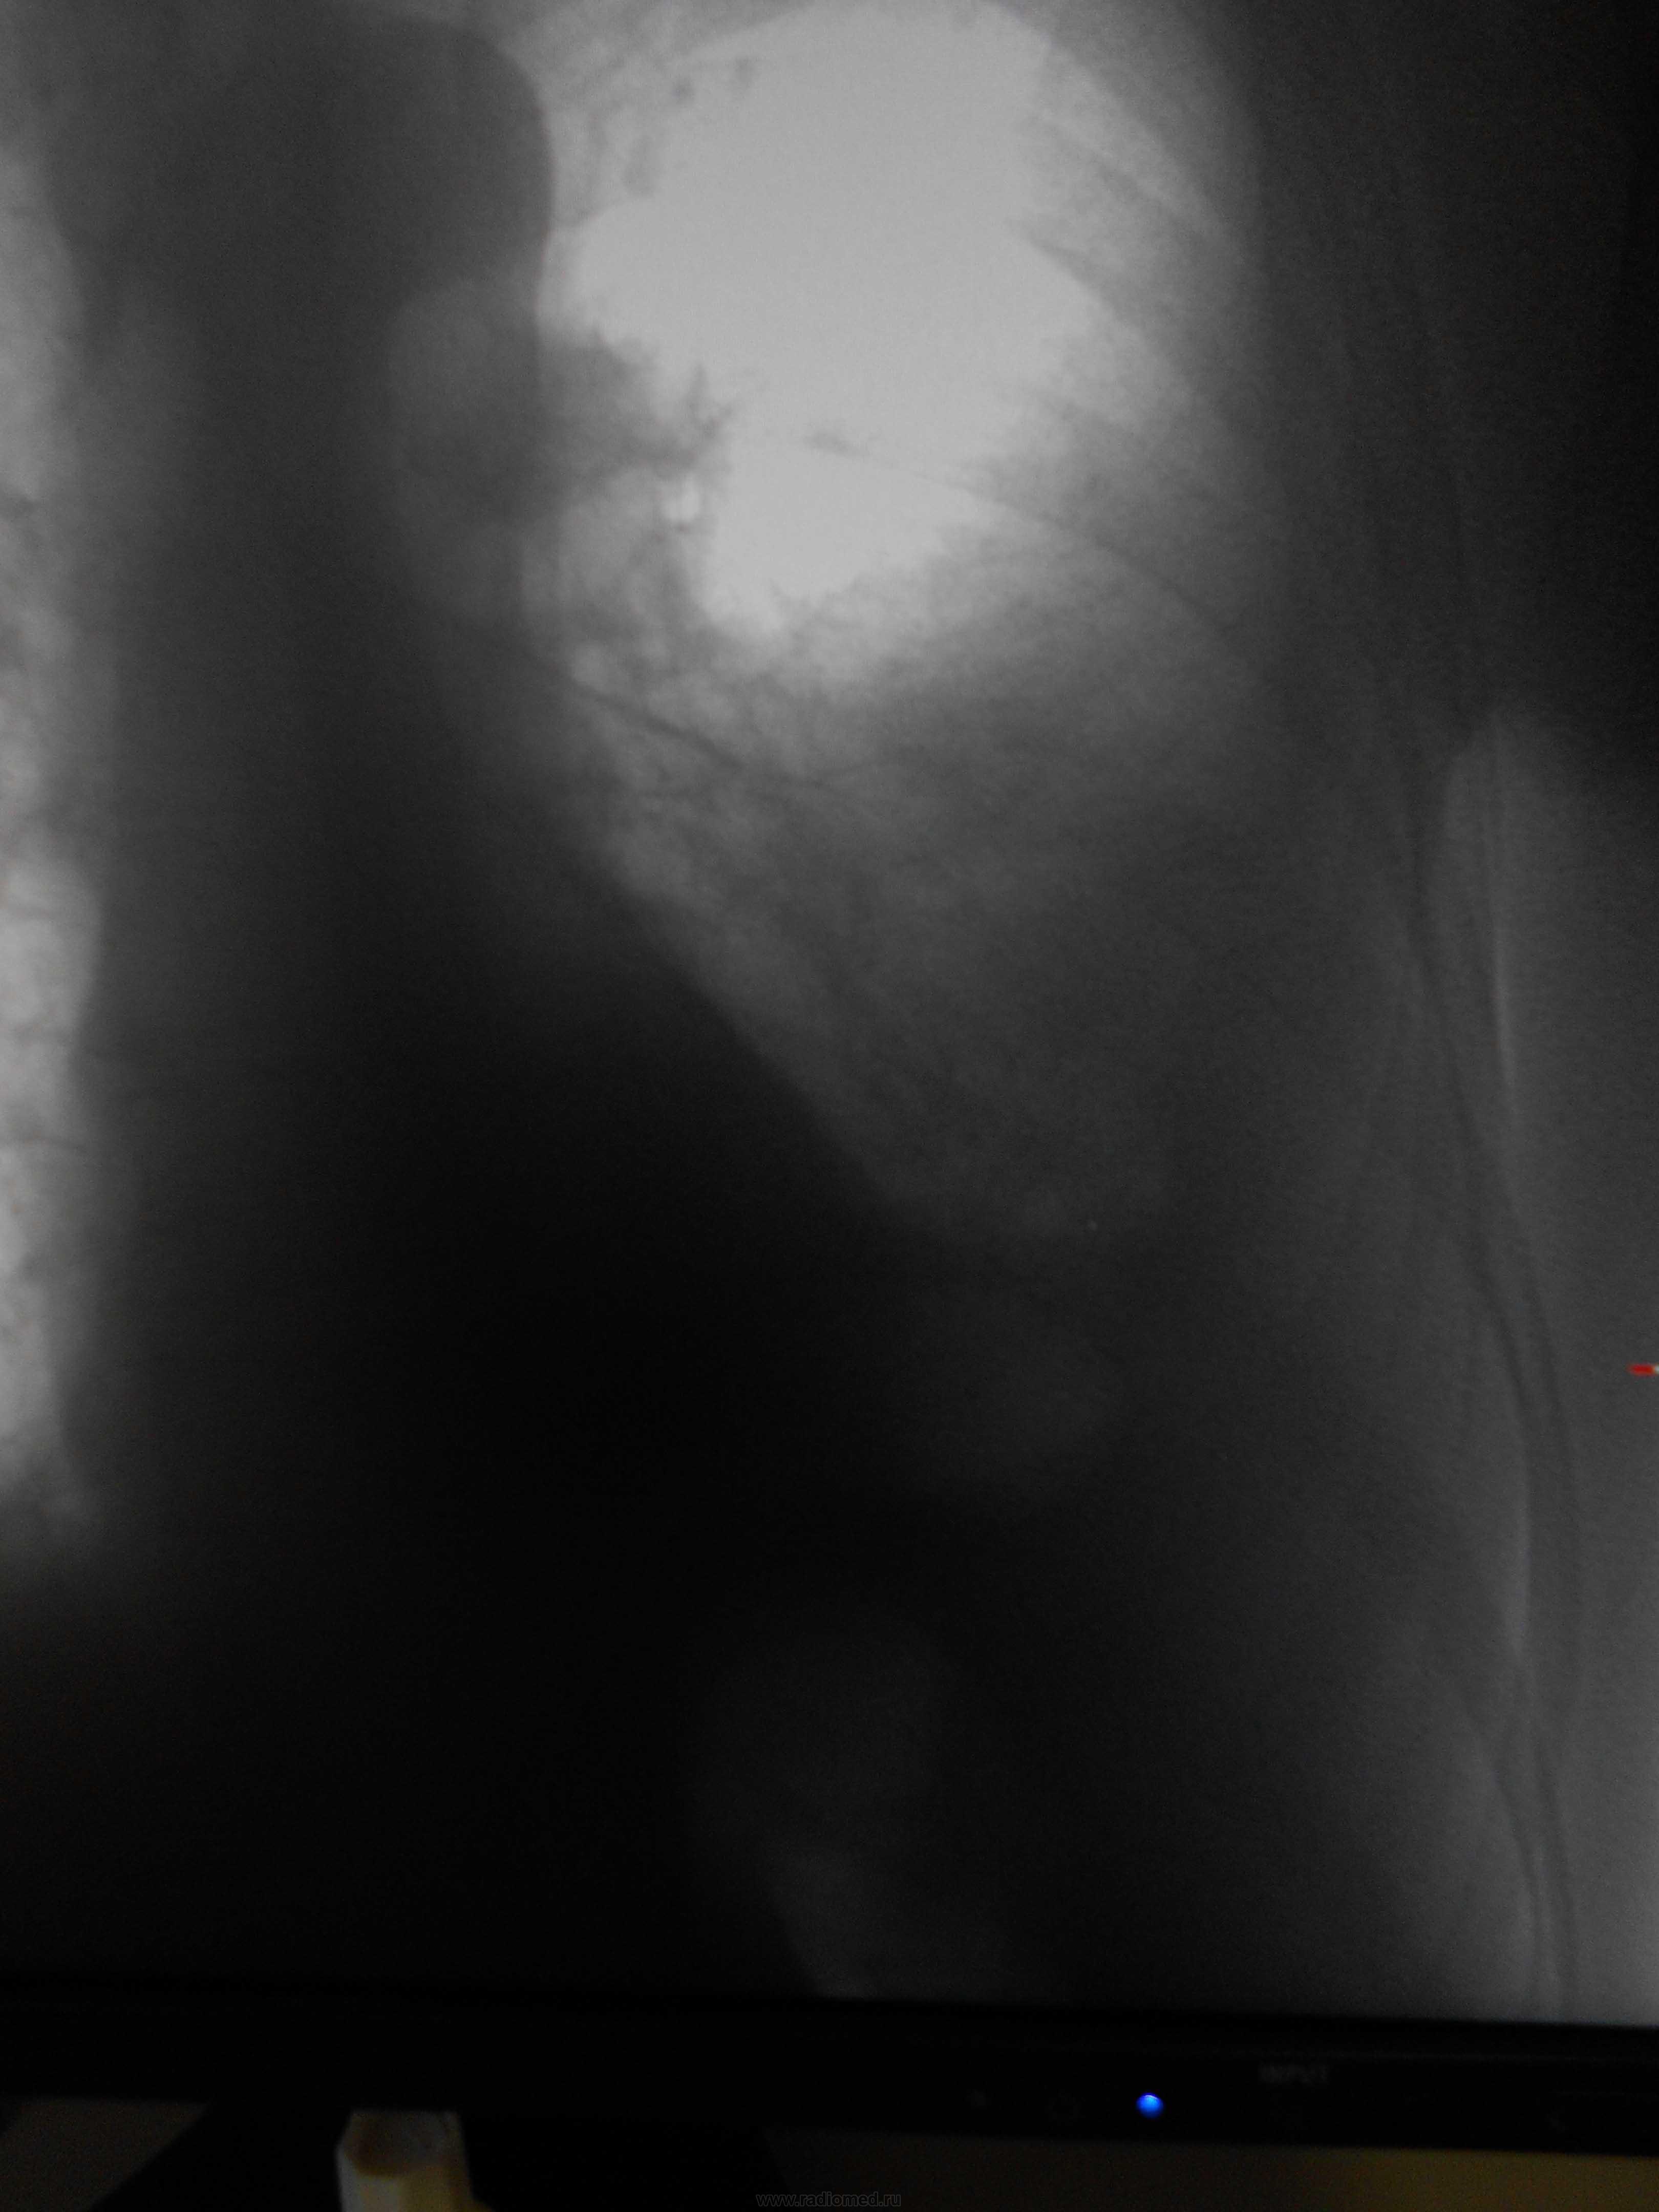

Пол пациента: Мужской пол Тип патологии: Другое Область исследования: Грудная клетка и верхние дыхательные пути Методы исследования: Rg Мужчина, 1983 года рождения, наркоман. Жалобы на затруднение дыхания, больше толком ничего не может сказать. Поставила просто показать, наверное это осумкованный плеврит, но очень уж форма причудливая) https://radiomed.ru/sites/default/files/styles/case_slider_image/public/user/16049/dscn0196-2.jpg?itok=VMOIZfz8 https://radiomed.ru/sites/default/files/styles/case_slider_image/public/user/16049/dscn0200-2.jpg?itok=jF8RVB_8 https://radiomed.ru/sites/default/files/styles/case_slider_image/public/user/16049/dscn0199-2.jpg?itok=d8mgQYPQ ID:25338 Пнд, 24/12/2012 - 21:04 #1 Катенёв Валенти... Не на сайте Был на сайте: 7 лет 2 недели назад Зарегистрирован: 22.03.2008 - 22:15 Публикации: 54876 Здравствуйте Мила! Задний паракостальный без сомнений! Пнд, 24/12/2012 - 23:58 #2 Наталия Васильевна Не на сайте Был на сайте: 5 лет 8 месяцев назад Зарегистрирован: 25.09.2011 - 09:02 Публикации: 754 Катенёв Валентин Львович wrote: Здравствуйте Мила! Задний паракостальный без сомнений! Согласна, вопрос как давно? Если процесс "свеженький"-может, пардон, шарахнуть в эмпиему в любой момент. Втр, 25/12/2012 - 01:11 #3 И.Бондаренко Не на сайте Был на сайте: 2 дня 13 часов назад Зарегистрирован: 13.09.2011 - 22:55 Публикации: 9206 Наталия Васильевна wrote: Катенёв Валентин Львович wrote: Здравствуйте Мила! Задний паракостальный без сомнений! Согласна, вопрос как давно? Если процесс "свеженький"-может, пардон, шарахнуть в эмпиему в любой момент. Пусть хирурги "шарахнут" пункцией. Тогда точно будете знать. Втр, 25/12/2012 - 03:06 #4 Mila85 Не на сайте Был на сайте: 3 года 1 месяц назад Зарегистрирован: 15.03.2012 - 16:59 Публикации: 1790 Катенёв Валентин Львович wrote: Здравствуйте Мила! Задний паракостальный без сомнений! Здравствуйте, мы на работе тоже так единогласно подумали. Давность неизвестна, пациент где-то частно наблюдается со своей зависимостью, туда и потопал

Задний паракостальный без сомнений!

Согласна, вопрос как давно? Если процесс "свеженький"-может, пардон, шарахнуть в эмпиему в любой момент.